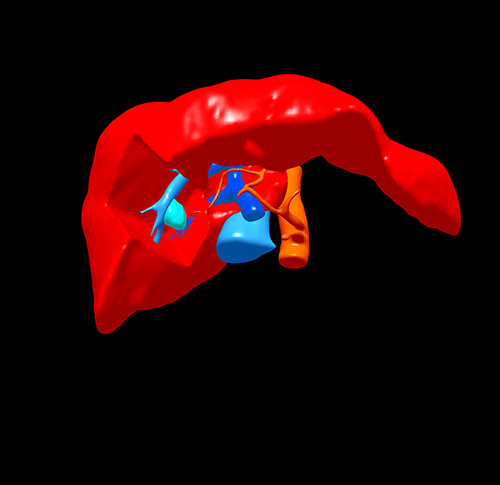

S5 肝癌--腹腔镜S5切除